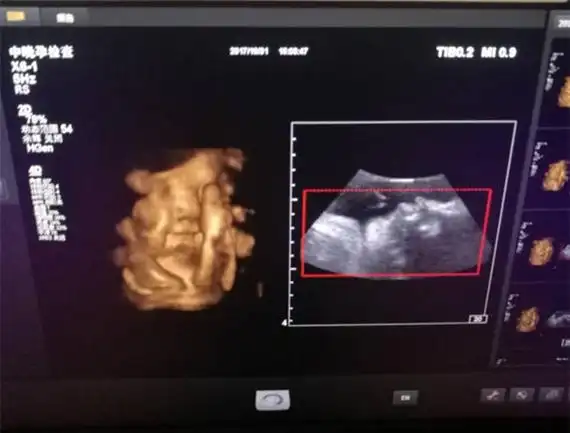

在b超中,怀孕第五个月的男孩和女孩有一个明显的区别:女孩可以看到

孕26周四维下睾丸的样子 如何看四维彩超识性别